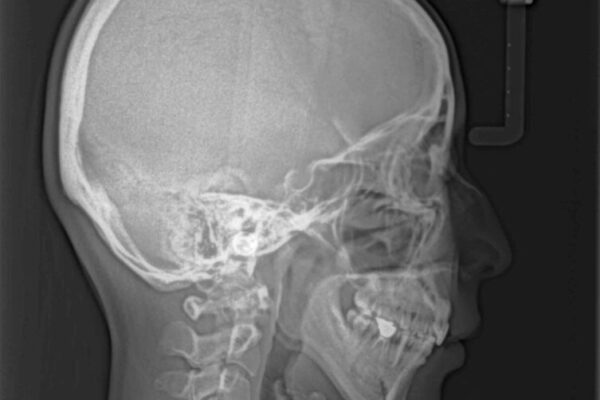

治療途中

• 【モニター】出っ歯と咬み合わせを改善 ワイヤー装置の抜歯矯正 治療途中画像